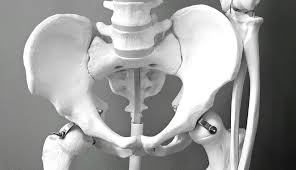

2) 영상검사와 보조 검사 🖼️

X선으로 관절 간격과 골극을 보고, MRI로 연골과 비구순, 힘줄 상태를 평가해요. 필요 시 초음파로 점액낭의 염증을 확인하고 주사 치료를 유도할 수 있어요. 염증성 질환이 의심되면 혈액검사도 병행해요.